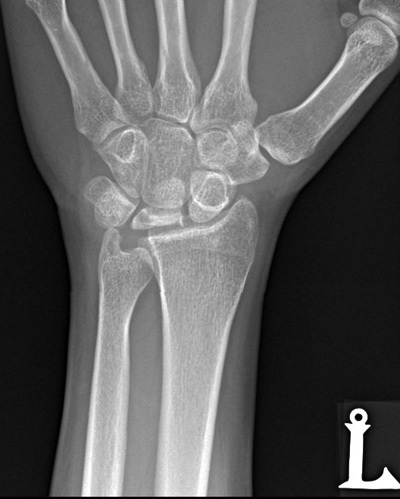

What conditions are associated with the pathological finding of this XR? What would you expect to find on physical exam?

Ulnar Positive Variance

What conditions are associated with the pathological finding of this XR?

Ulnar Negative Variance